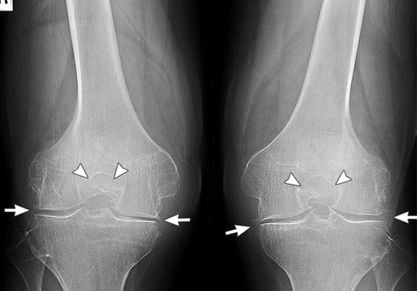

ЛФК при гонартрозе коленного сустава: правила выполнения упражнений. Противопоказания к выполнению некоторых упражнений. Техника выполнения комплекса упражнений по Бубновскому.